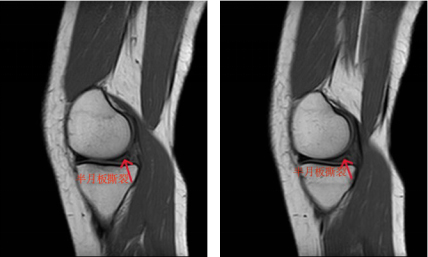

▲术前右膝关节冠状位核磁可见

半月板在多个层面上出现高信号

(红色箭头所指位置)